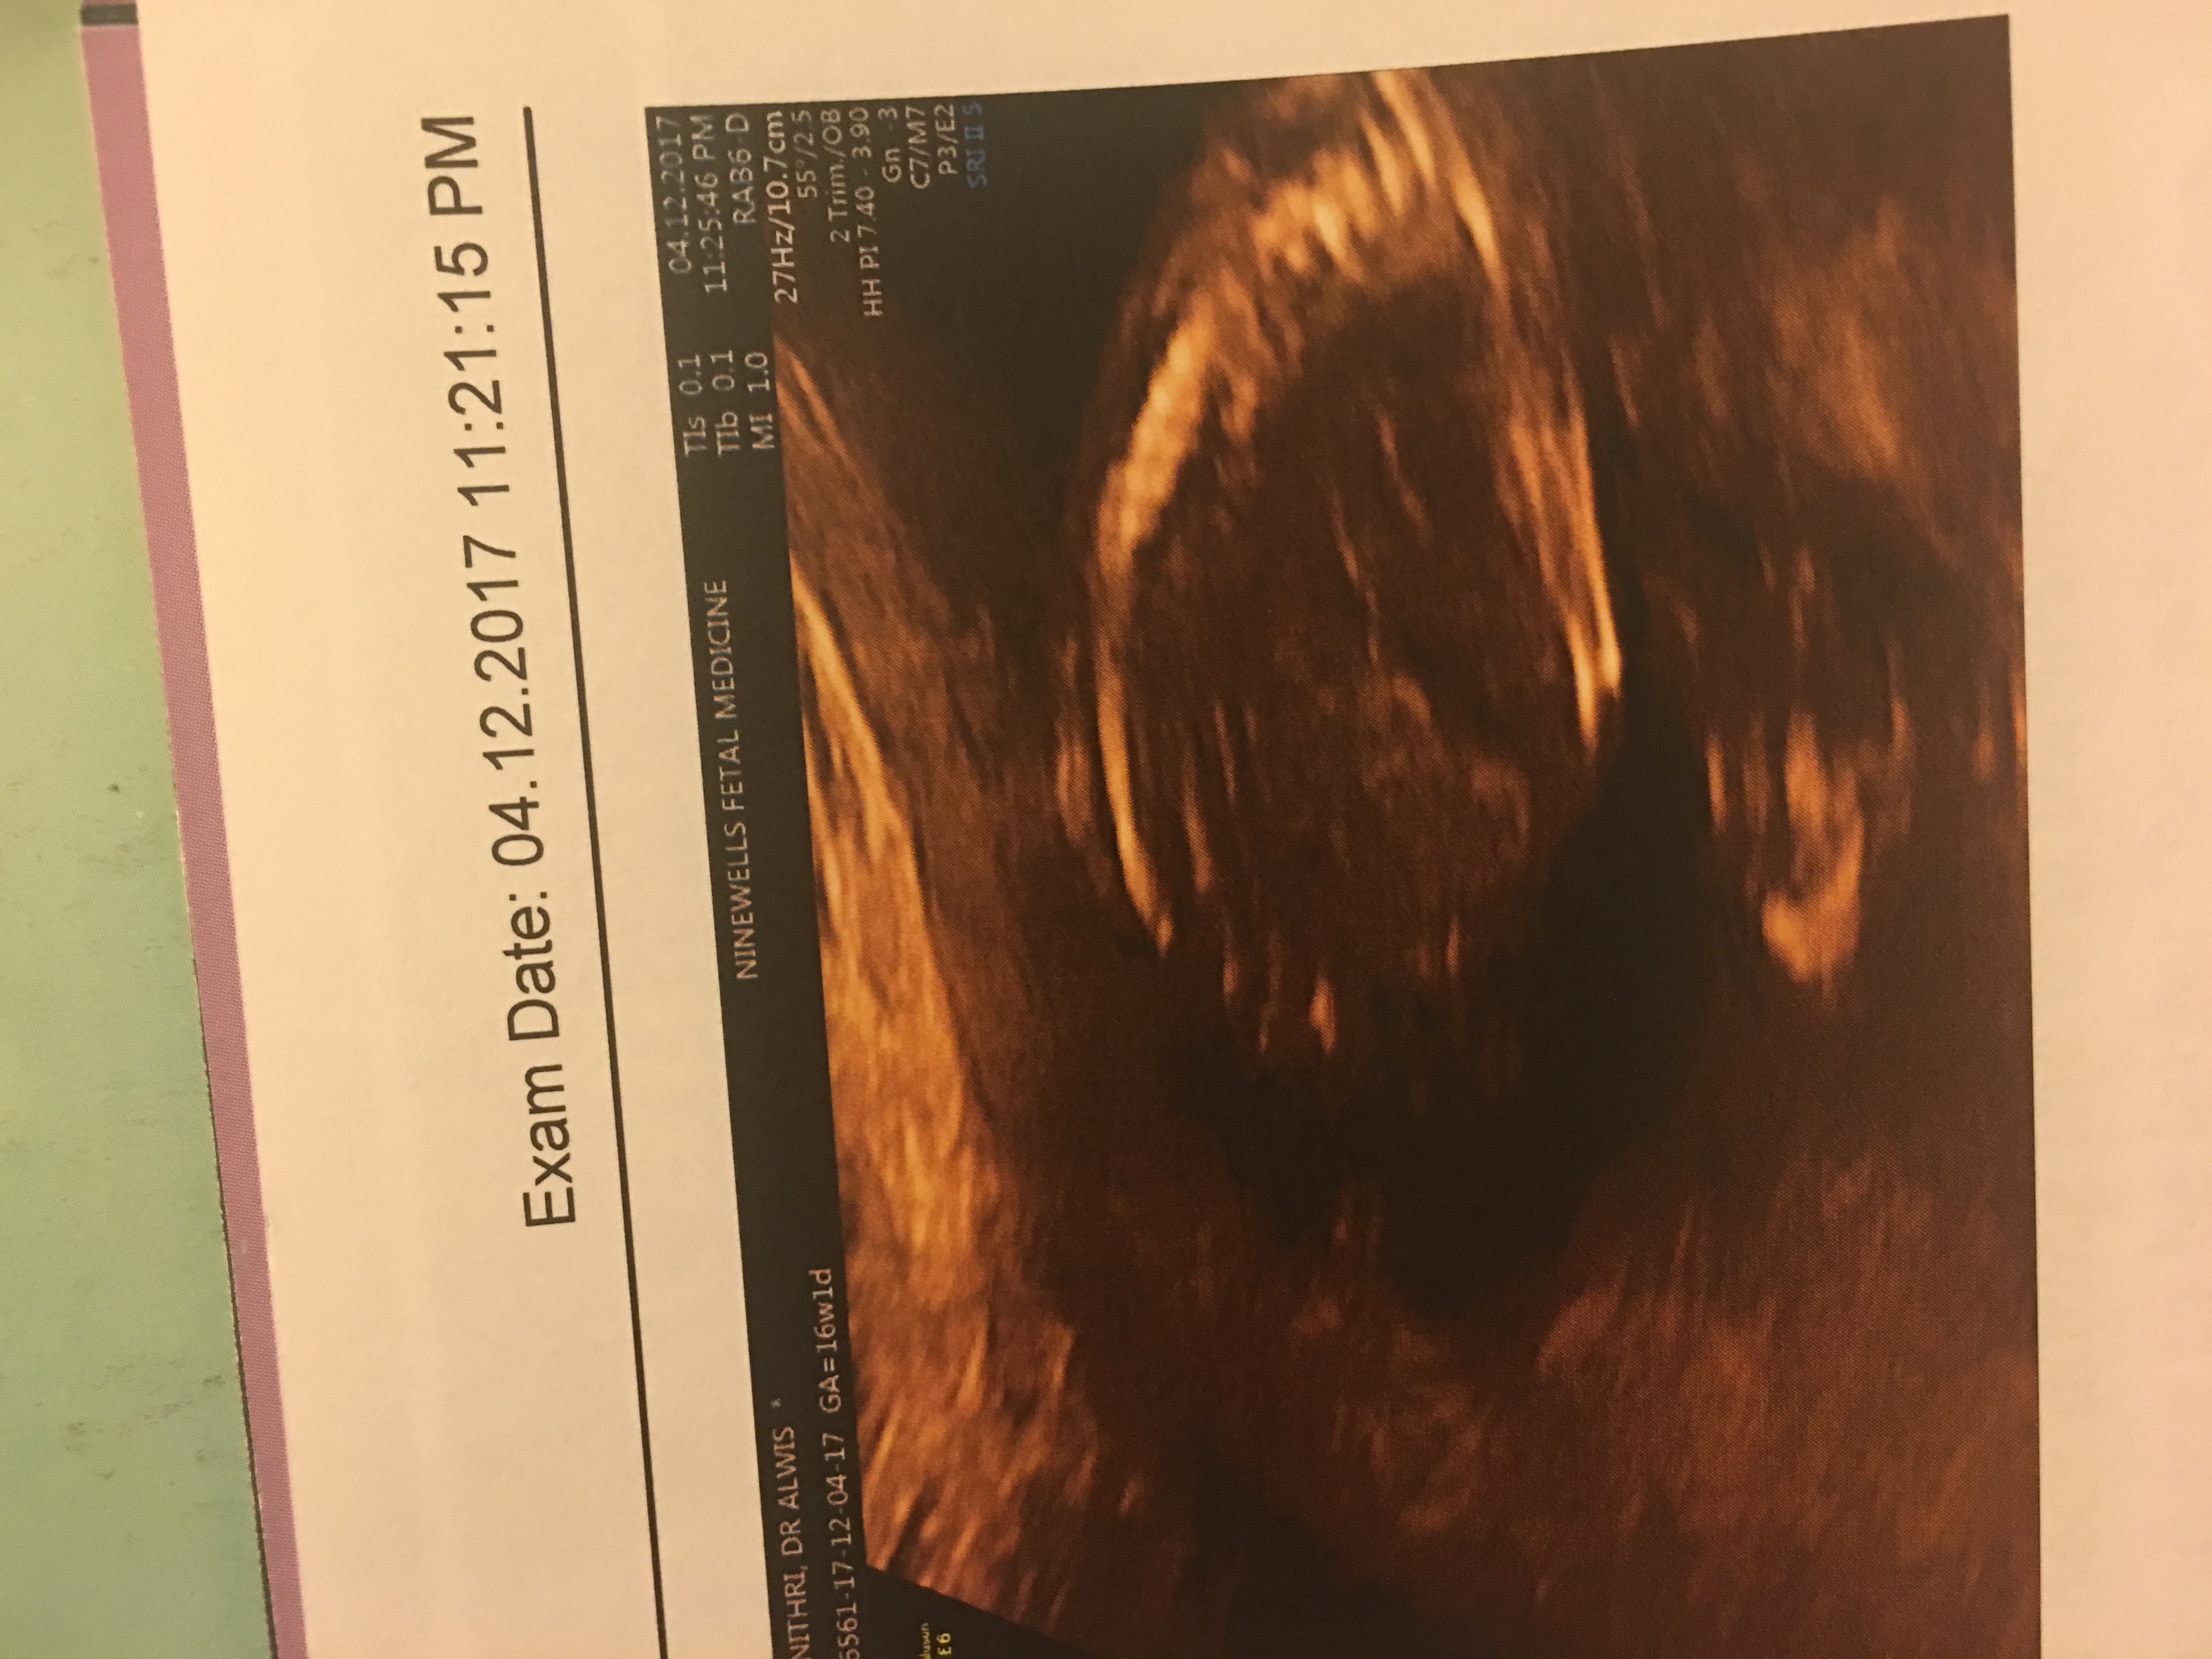

Boy or girl? Attachment 39452Attachment 39452Attachment 39452Attachment 39452Attachment 39452Attachment 39452